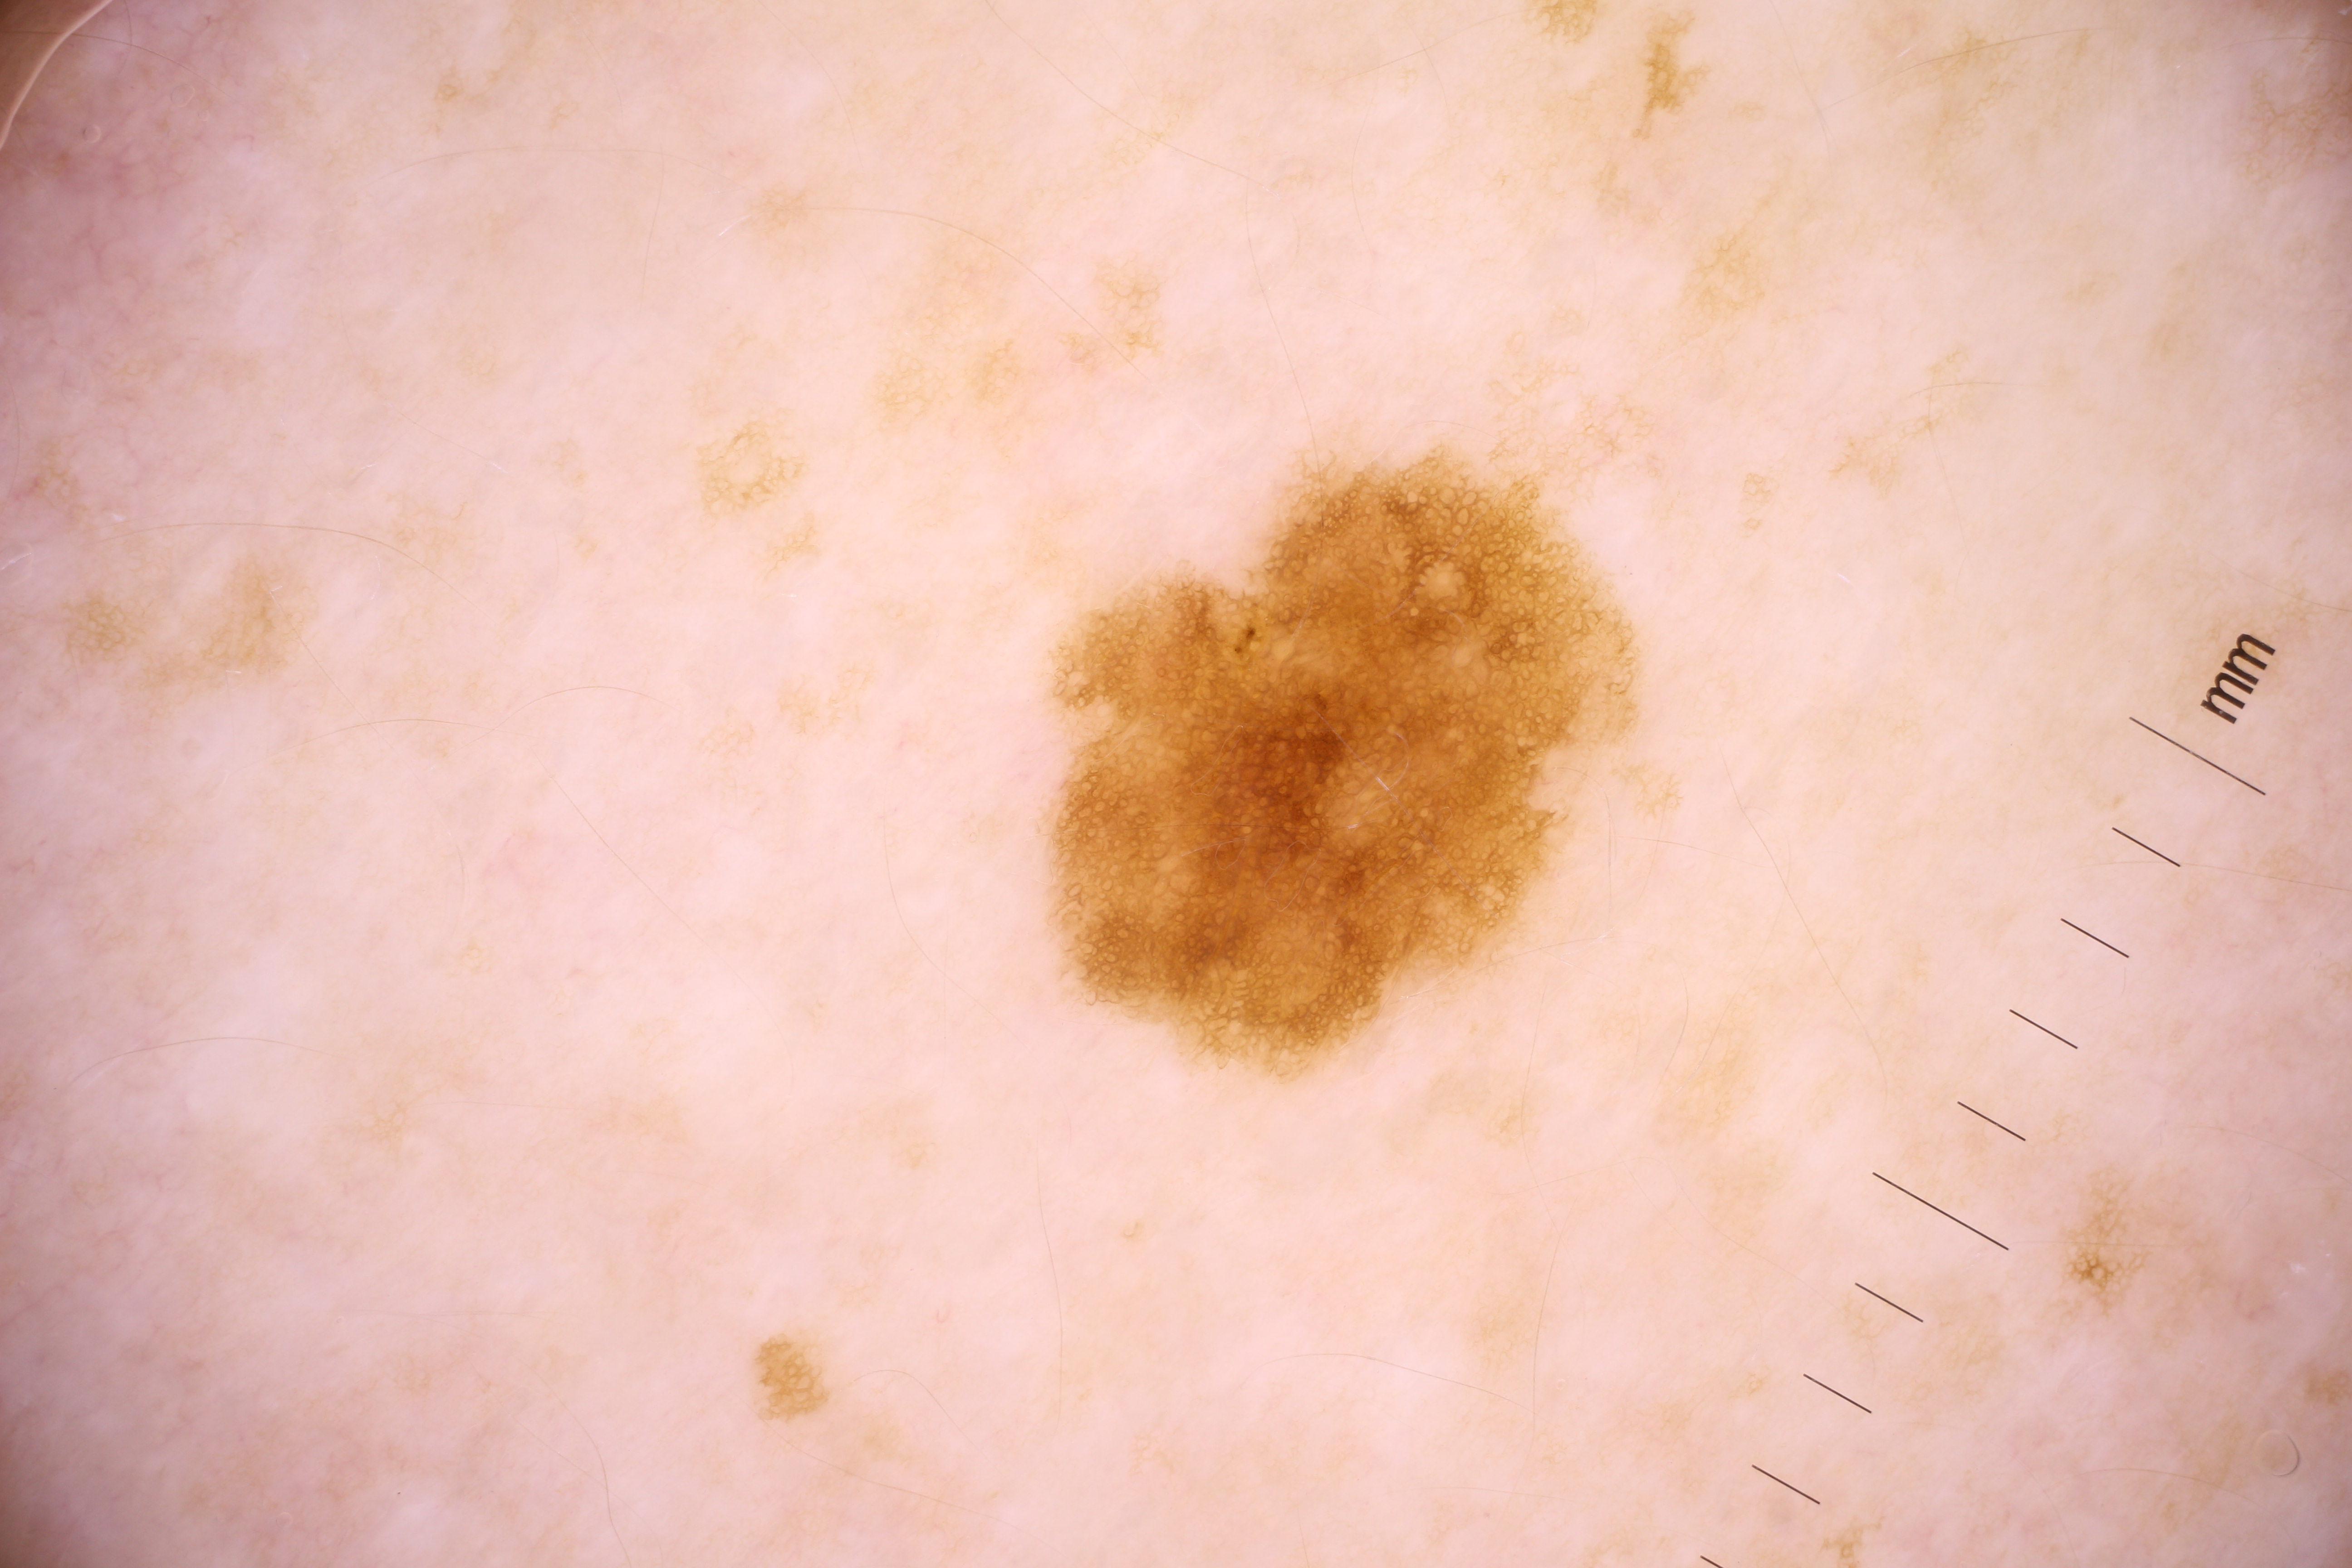

{

"acquisition_day": 1,

"age_approx": 55,

"anatom_site_general": "upper extremity",

"concomitant_biopsy": true,

"diagnosis_1": "Malignant",

"diagnosis_2": "Malignant melanocytic proliferations (Melanoma)",

"diagnosis_3": "Melanoma in situ",

"diagnosis_confirm_type": "histopathology",

"image_manipulation": "instrument only",

"image_type": "dermoscopic",

"lesion_id": "IL_6419891",

"melanocytic": true,

"patient_id": "IP_7770500",

"sex": "male"

}